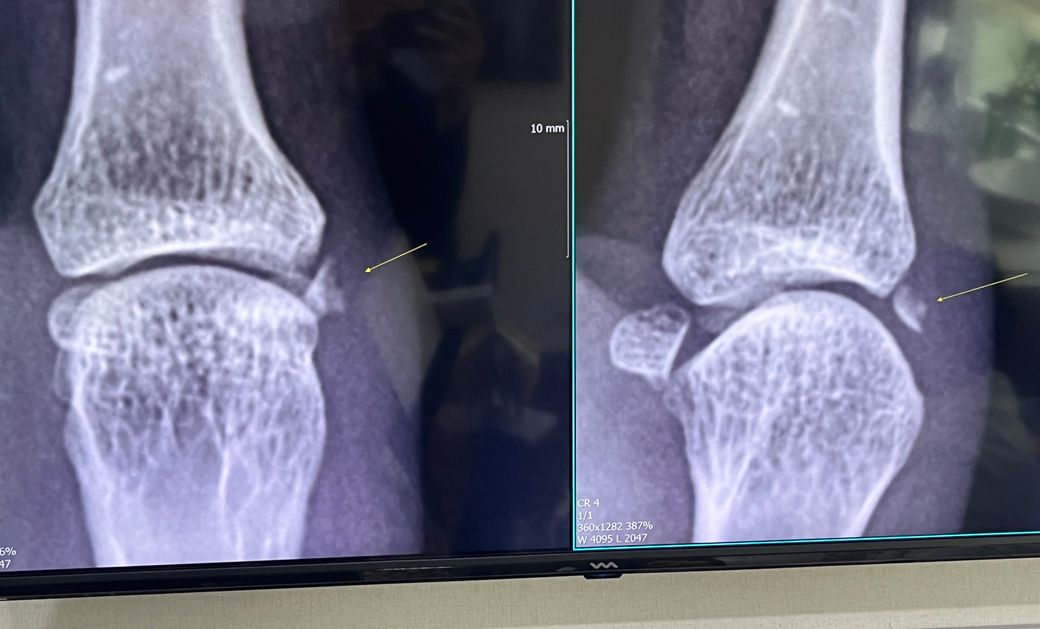

엄지손가락 골절 일반정형외과를 가도 될까요?

뼈조각이 약 5mm정도인데 수부외과를 가는게 좋을까요? 아니면 일반 정형외과에서 수술해도 괜찮을까요?

뼈조각이 작아서 일반 정형외과에도 수술해도 예우가 괜찮을지 문의드립니다

• 1번 째 사진

5mm 크기의 뼈 조각이 있는 경우, 일반 정형외과에서도 충분한 진료와 치료를 받을 수 있습니다. 대부분의 정형외과 전문의들은 손가락 골절과 같은 기본적인 골절 치료에 경험과 지식을 갖추고 있습니다. 그러나 골절이 복잡하거나 특수한 경우, 예를 들어 관절 손상이 동반되었거나 뼈 조각이 여러 개인 경우에는 수부 전문의(손을 전문적으로 다루는 외과 의사)의 평가가 필요할 수 있습니다. 수부 전문의는 손과 손목의 복잡한 구조와 기능에 대한 특별한 전문 지식을 갖고 있어, 더 복잡하고 섬세한 치료가 필요한 경우에 적합합니다. 경험이 많은 전문의가 있는 곳인지는 사전에 알아보시고 방문하시기 바랍니다.